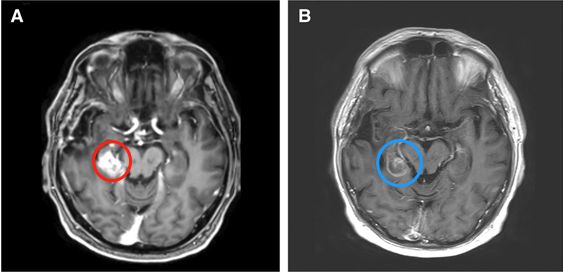

在60°C時會發(fā)生凝結(jié)性壞死引起的瞬時細(xì)胞死亡。在43°C至60°C之間的溫度下,時間和溫度的組合主要通過凋亡導(dǎo)致細(xì)胞死亡。這兩個系統(tǒng)至少部分地依賴于要消融的病變的對比光學(xué)特性以及要保留的周圍更正常的腦組織。結(jié)果,所產(chǎn)生的病變可以相對符合目標(biāo)病變的邊界。此外,這兩個LITT系統(tǒng)還利用了自然散熱器(例如相鄰的溝和水箱以及周圍的血管系統(tǒng))的優(yōu)勢,以防止熱量傳播到潛在的雄辯結(jié)構(gòu)(圖1和2)。LITT可以消融鉆孔開顱手術(shù)和傳統(tǒng)的開放式手術(shù)都難以進(jìn)入得深部病變(圖3)。由于溫度梯度迅速下降到消融區(qū)域之外,因此周圍正常的腦組織無需進(jìn)行熱消融。

圖1:68歲男性,膠質(zhì)母細(xì)胞瘤術(shù)后復(fù)發(fā),LITT術(shù)消融前(A)和消融后(B)。請注意,消融區(qū)局限在周圍的腦池,保護(hù)了鄰近的腦干不受損傷。